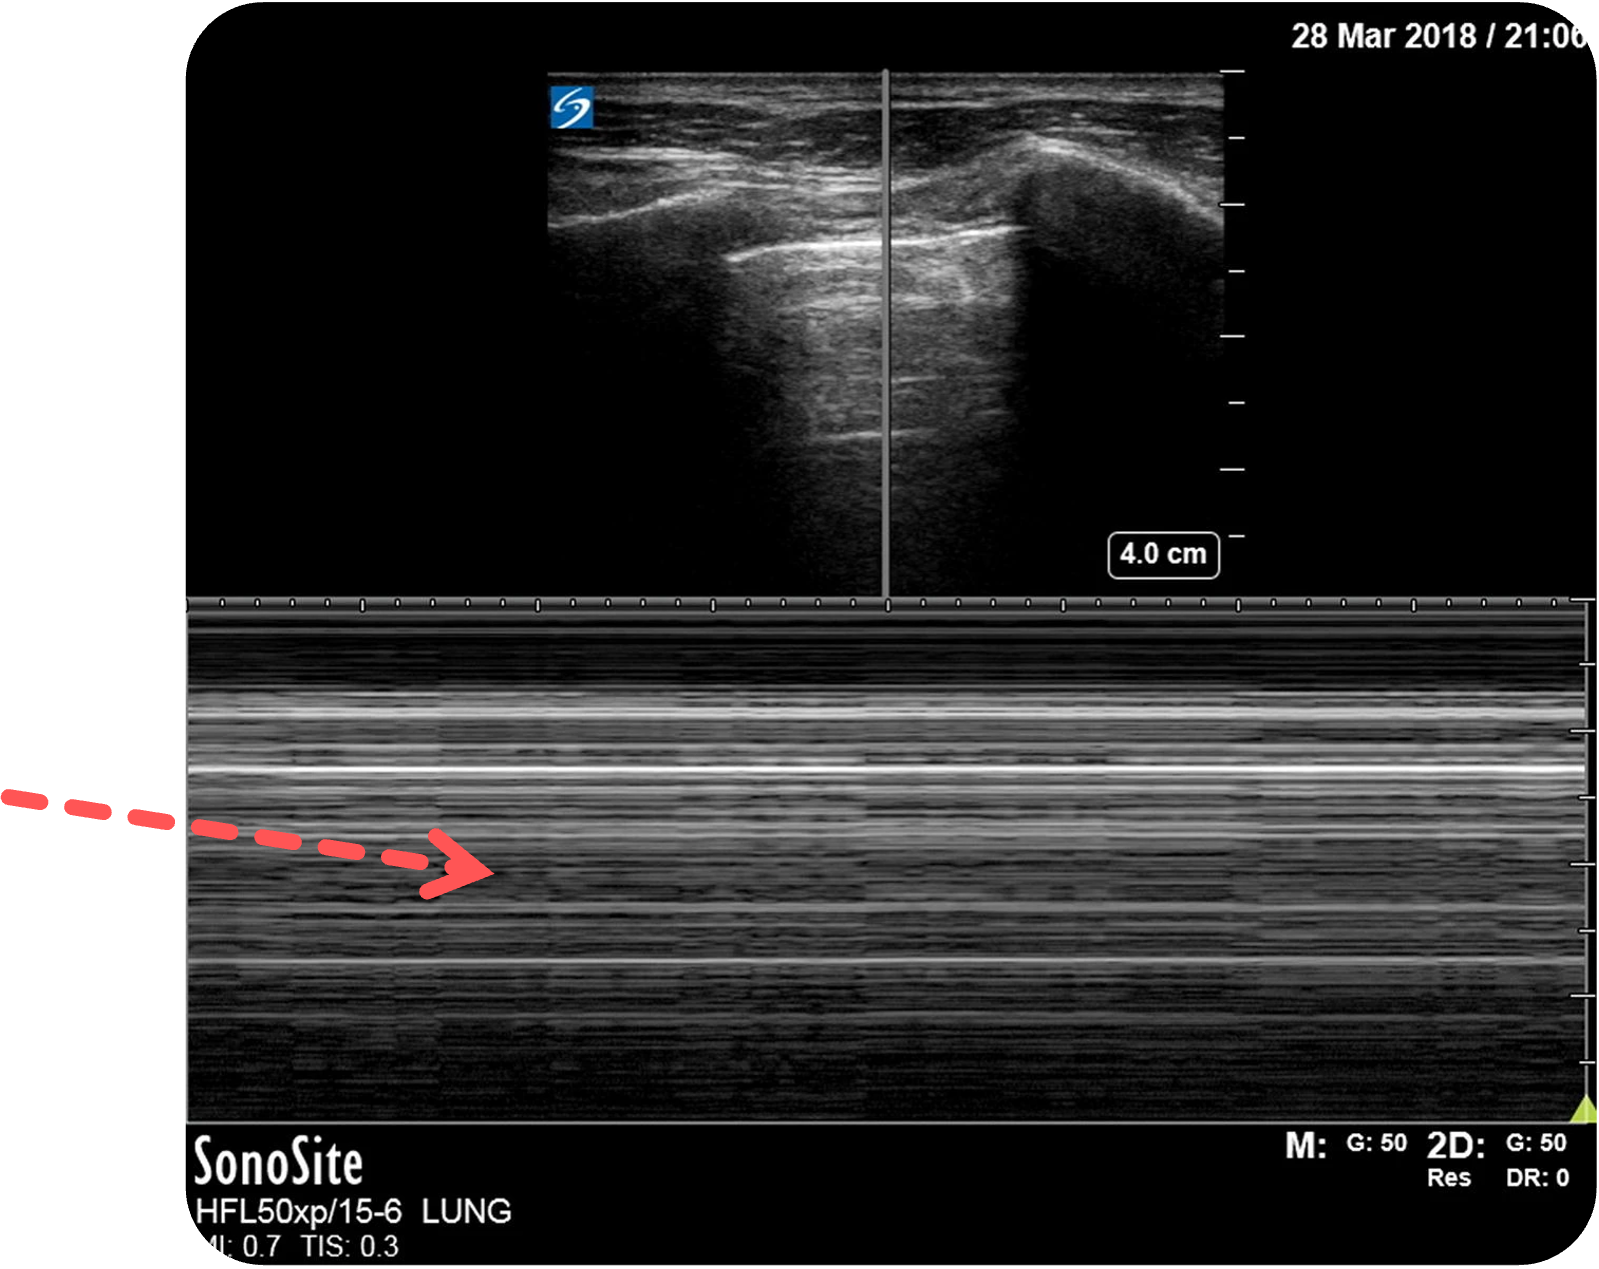

Pneumothorax im M-Mode :

Im M-Mode

Statt des Seashore-Zeichens zeigt sich ein homogenes, horizontal gestreiftes Muster über das gesamte Bild – das sogenannte Barcode- oder Stratosphären-Zeichen.

Dieses Muster weist auf einen fehlenden pleuralen Kontakt hin und ist damit hochverdächtig auf einen Pneumothorax

Figure 5 (links) und Figure 3 (rechts) aus Ketelaars, Rein., Reijnders, G., van Geffen, GJ. et al. ABCDE of prehospital ultrasonography: a narrative review. Crit Ultrasound J 10, 17 (2018). https://doi.org/10.1186/s13089-018-0099-y. Teilausschnitt des Originalbilds. Es wurden die Beschriftungen ergänzt.